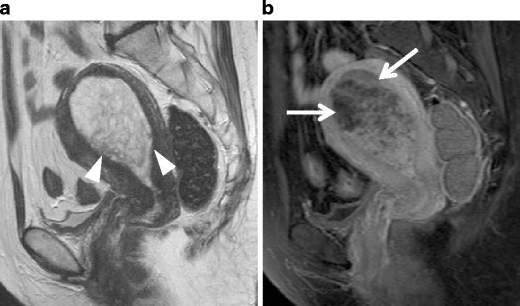

Endometrial polyp in a 52-year-old woman, who is taking Tamoxifen for her pervious breast cancer. a Sagittal T2-weighted image shows a well-defined polypoid tumor of high intensity (arrowheads), containing fine reticular network of low intensity. b Postcontrast T1-weighted image shows unenhanced areas, representing cystic spaces (arrows)

Adenomyoma in a 40-year-old woman. a Sagittal T2-weighted image demonstrates a polypoid mass of decreased intensity in the endometrium (arrows), containing cystic space of bright intensity. The myometrium in the anterior wall and fundus is diffusely thickened by simultaneous adenomyosis. b T1-weighted image shows high intensity corresponding to the cystic space, suggesting the hemorrhagic fluid within the mass